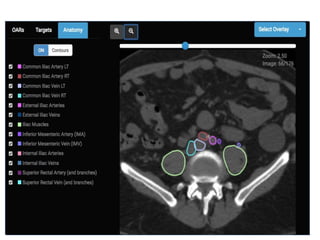

• Now turn off ALL contours

• Start at abdominal aorta

• Scroll inferiorly, following

branches

• Lymph nodes sit on vessels.

This is why we contour

vessels in nodal CTV

• Sequence of vessels:

– Aorta (artery) or IVC (vein) 

Common Iliacs (R and L) 

Internal iliac (go posterior/in

front of sacrum) and External

Iliacs (go anterior  become

inguinal/femoral when exit

pelvis)

Review anatomy of pelvic vessels